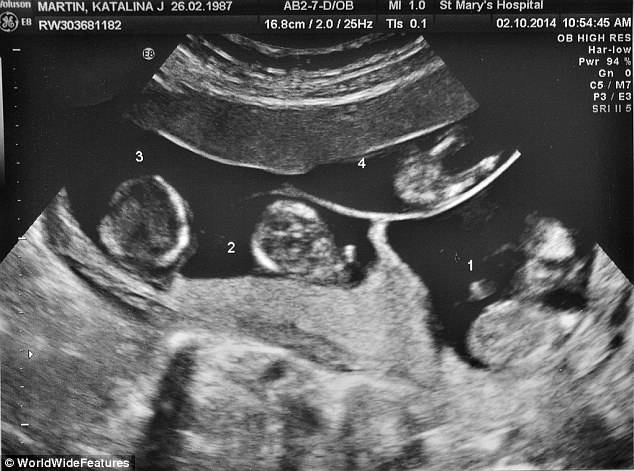

Unimamme, oggi dobbiamo parlarvi di un evento straordinario riguardante un bellissimo quartetto di bambini inglesi tutti gemelli: Aston, Sofia, Amelia e Roman.

Il fatto ancor più straordinario è che i 4 piccini sono nati in modo naturale ciascuno da un uovo diverso.

Si tratta, come intuirete, di un evento rarissimo perché solo 3 o 4 parti quadrigemellari nascono ogni anno nel Regno Unito e solitamente accade quando un uovo si divide nel grembo materno.

Questo significa che 2 o 3 bambini della quartina sono nati dallo stesso uovo e che quindi sono identici.

Le probabilità di un quartetto di bimbi è di 1 a 700 mila ma gli esperti asseriscono di non poter fare stime su quartetti non identici.